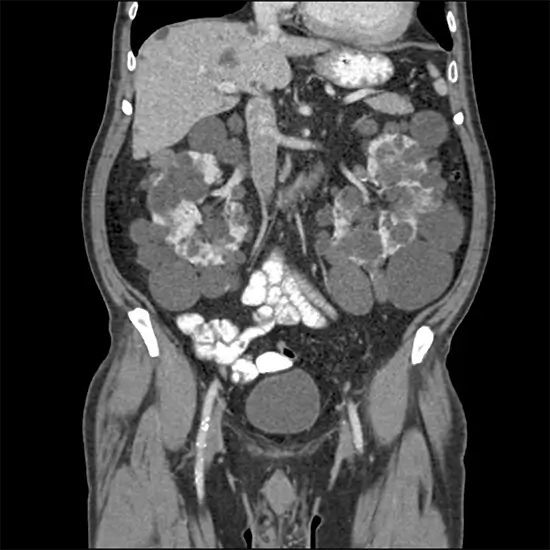

CT scans the body quickly and accurately, including the pelvis and areas near the pelvis. The test can be used to diagnose or detect the following:

• Tumours or masses, including cancer

• The origin of pelvic pain

• pelvic laceration